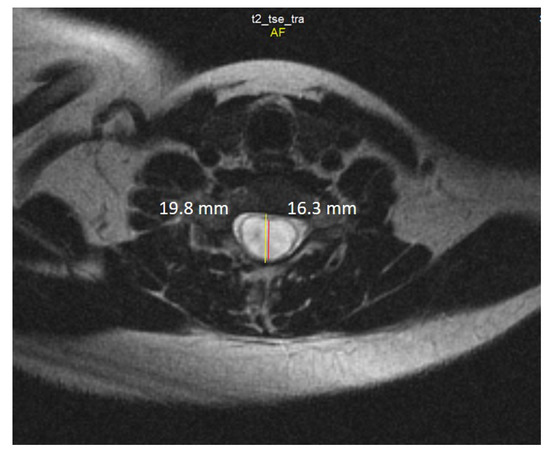

Chiari 1 Malformation (CM1) is classically defined as a caudal displacement of the cerebellar tonsils through the foramen magnum into the spinal cord. Modern imaging techniques and experimental studies disclose a different etiology for the development of CM1, but the main etiology factor [...] Read more.

Chiari 1 Malformation (CM1) is classically defined as a caudal displacement of the cerebellar tonsils through the foramen magnum into the spinal cord. Modern imaging techniques and experimental studies disclose a different etiology for the development of CM1, but the main etiology factor is a structural defect in the skull as a deformity or partial reduction, which push down the lower part of the brain and cause the cerebellum to compress into the spinal canal. CM1 is classified as a rare disease. CM1 can present with a wide variety of symptoms, also non-specific, with consequent controversies on diagnosis and surgical decision-making, particularly in asymptomatic or minimally symptomatic. Other disorders, such as syringomyelia (Syr), hydrocephalus, and craniocervical instability can be associated at the time of the diagnosis or appear secondarily. Therefore, CM1-related Syr is defined as a single or multiple fluid-filled cavities within the spinal cord and/or the bulb. A rare CM1-related disorder is syndrome of lateral amyotrophic sclerosis (ALS mimic syndrome). We present a unique clinical case of ALS mimic syndrome in a young man with CM1 and a huge singular syringomyelic cyst with a length from segment C2 to Th12. At the same time, the clinical picture showed upper hypotonic-atrophic paraparesis in the absence of motor disorders in the lower extremities. Interestingly, this patient did not have a disorder of superficial and deep types of sensitivity. This made it difficult to diagnose CM1. For a long time, the patient’s symptoms were regarded as a manifestation of ALS, as an independent neurological disease, and not as a related disorder of CM1. Surgical treatment for CM1 was not effective, but it allowed to stabilize the course of CM1-related ALS mimic syndrome over the next two years. Full article